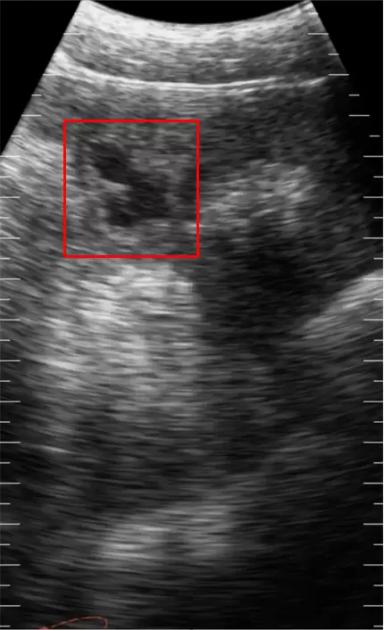

Расшифровка вчерашнего УЗИ снимка

Доброе утро коллеги!

На неделю пропаду, так как улетаю в Сибирь обучать клиентов.

Однако, не могу не рассказать что же было изображено на вчерашнем интерактивном снимке.

Интерактив по УЗИ!)

Всем доброго времени суток!

Сегодня без постов и знаний, просто предлагаю Вам угадать , какой орган визуализирован на снимке!)

Подсказки - это КРС, мясное направление, ...

Орган также связан с репродуктивной системой ...

Возвращаясь к Вашему комментарию, соглашусь по поводу 3го случая, он очень спорный и разные специалисты будут его трактовать по разному.

И касательно этого снимка, я согласен что также (как трабекулы) могут светиться лизированные эритроциты, полость обычно схлопывается и заростает через 20-30 дней, (около 90%).